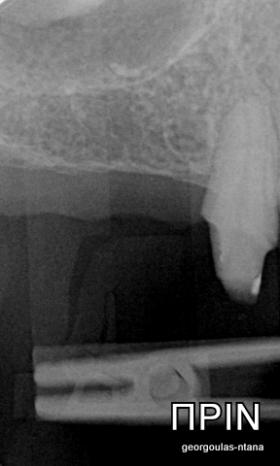

Ο ασθενής  προσήλθε στο ιατρείο μας θέλοντας να βελτιώσει την εμφάνιση των πρόσθιων δοντιών του και να αποκαταστήσει την υγεία κ την λειτουργία όλου του στόματος. Πραγματοποιήθηκε περιοδοντική θεραπεία κ ενδοδοντικές θεραπείες (απονευρώσεις) όπου κρίθηκε απαραίτητο και στη συνέχεια τοποθετήθηκαν 3 εμφυτεύματα, 2 δεξιά στις θέσεις του πρώτου κ δεύτερου γομφίου κ 1 αριστερά στη θέση του πρώτου προγομφίου. Κατά την  τοποθέτηση των 2 εμφυτευμάτων της δεξιάς πλευράς, πραγματοποιήθηκε κλειστή ανύψωση ιγμορείου με το σύστημα Piezotome-Intralift , τεχνική που εξασφαλίζει τη μικρότερη δυνατή επέμβαση κ τη μικρότερη μετεγχειρητική ταλαιπωρία (minimally invasive), καθώς κ αυξητικους παράγοντες PRF. Σε όλη τη διάρκεια της θεραπείας  ο ασθενής ήταν καλυμμένος τόσο αισθητικά όσο και λειτουργικά με προσωρινές μεταβατικές αποκαταστάσεις. 4 μήνες μετά την  τοποθέτηση των εμφυτευμάτων κ την οστεοενσωμάτωσή τους, ακολούθησε η τοποθέτηση των μόνιμων αποκαταστάσεων.